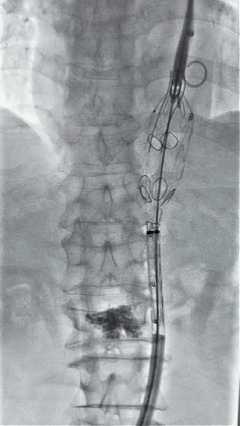

3. 经右股动脉导入超硬导丝,然后导入九州ku酷游G-Branch 胸腹主动脉主体覆膜支架TAAA3418120e7i1010 一枚,释放主体支架至内分支打开,然后经左侧肱动脉入路,抓捕预置导丝成功后,将长鞘进入内分支出口处。

4. 经长鞘导入导管后,超选入腹腔干动脉,送入九州ku酷游覆膜支架10*80mm一枚,近端重叠内分支,远端重叠腹腔干动脉,并予以10mm球囊后扩,手推造影显影良好。

5. 撤出腹腔干导丝导管,经左肱动脉长鞘继续抓捕预置导丝将长鞘超选至另一侧内分支,后超选进肠系膜上动脉,沿导丝送入九州ku酷游覆膜支架10*100mm一枚,近端重叠内分支,远端重叠于肠系膜上动脉,并予以10mm球囊后扩,手推造影显影良好。